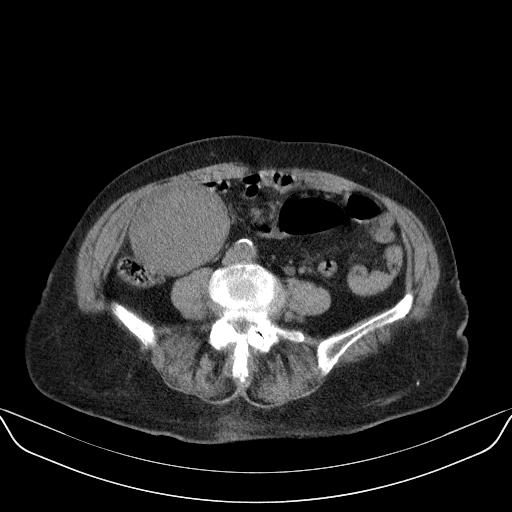

以下是引用林建春在2010-3-11 17:21:00的发言:[br]病变边界较清晰,看见明显包膜,考虑良性占位性病变。[br][br]期待病理结果!

以下是引用yuhongjun在2010-3-12 6:32:00的发言:[br]回肠末端间质瘤,不除外阑尾粘液囊腺瘤,臀部注射性肉芽肿钙化. [br] [br]